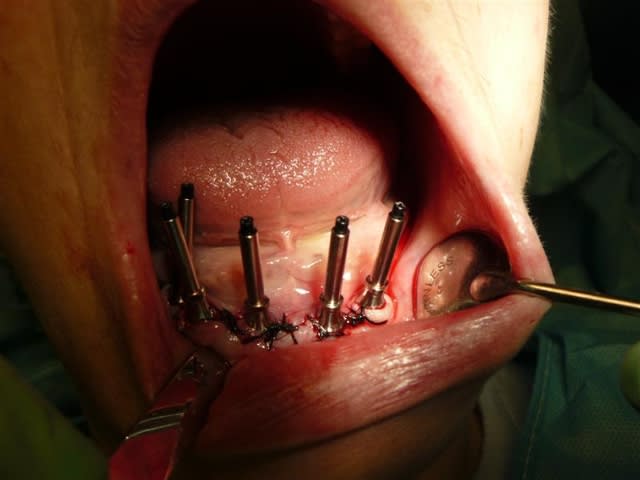

05/02/2009 à 14h24

premières étapes ce matin,... la suite ce soir...

P1020006  medium  a0zufu - Eugenol

P1020053  medium  blnmxy - Eugenol

P1020061  medium  gdiw3c - Eugenol

P1010895  medium  hvrt9v - Eugenol

P1010904  medium  ujf9t1 - Eugenol

c'est beauuuu !

un p'ti conseil si je puis me permettre;

fais toi faire une réplique de la future prothèse en résine transparente et évide le couloir prothétique.

c'est plus facile pour positionner tes implants.

on attend la suite des photos.